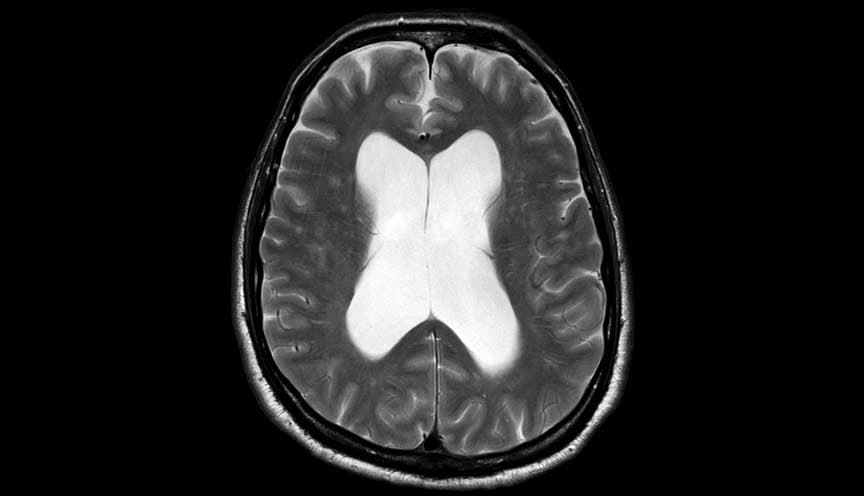

استسقاء الرأس سوي الضغط

استسقاء الرأس سوي الضغط (NPH)